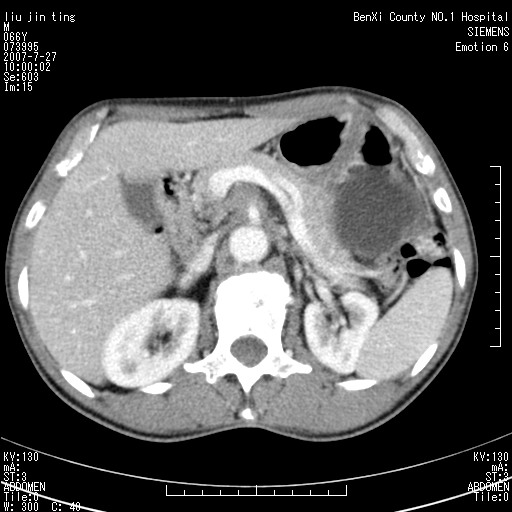

腹痛,背痛,无恶心呕吐,不黄,彩超示胰腺钩癌,ct扫描病灶平扫30-40hu,增强后动脉期40--60hu,静脉期50-68hu,真的是钩突上的么?您要试一试么?

动脉期

静脉期